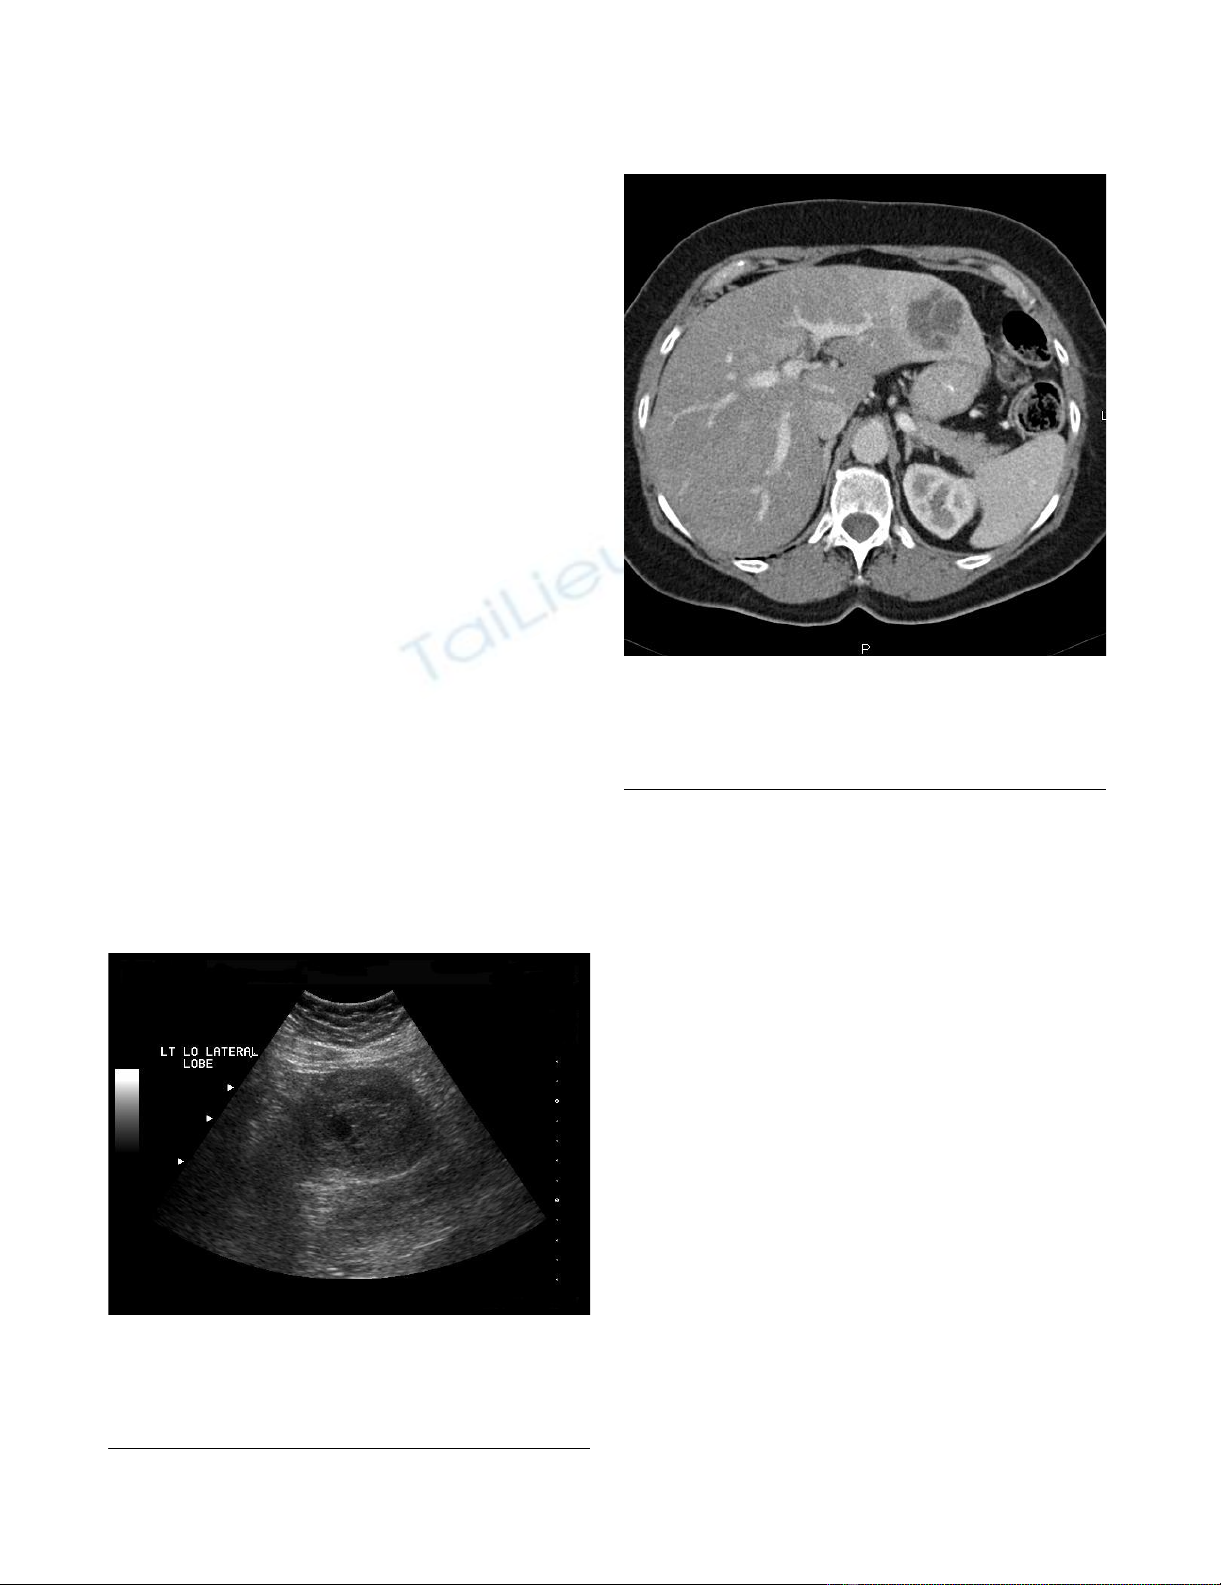

Diagnostic imaging included an abdominal ultrasound

(Figure 1) which revealed a heterogeneous solid mass in

the lateral segment of the left hepatic lobe measuring 6.3

× 5.3 × 5.0 cm. A CT scan with intravenous contrast was

obtained which revealed a 4.9 × 4.9 cm enhancing, poorly

marginated mass in segment II of the liver, with no other

intra-abdominal masses or lymphadenopathy (Figure 2).

Ultrasound of the abdomen; Ultrasound of the abdomen depicting a 6.3 × 5.3 × 5.0 heterogenous solid mass in the lat-eral segment of the left lobe of the liverFigure 1

Ultrasound of the abdomen; Ultrasound of the abdo-

men depicting a 6.3 × 5.3 × 5.0 heterogenous solid

mass in the lateral segment of the left lobe of the

liver.

CT scan of the abdomen and pelvis; CT scan of the abdomen and pelvis with IV contrast demonstrates a 4.9 × 4.9 cm enhancing, poorly marginated mass in segment II of the liverFigure 2

CT scan of the abdomen and pelvis; CT scan of the

abdomen and pelvis with IV contrast demonstrates a

4.9 × 4.9 cm enhancing, poorly marginated mass in

segment II of the liver.